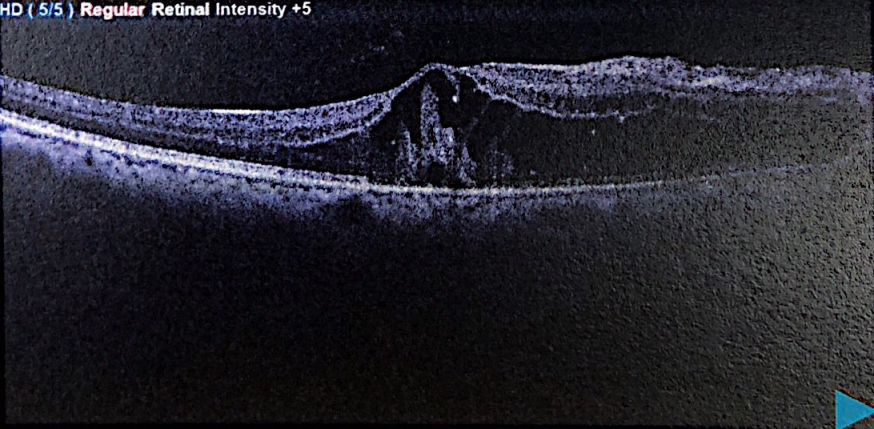

The patient was admitted, laboratory results obtained are shown in Table 1 [Tab. 1]. Optical coherence tomography (OCT) (Figure 2 [Fig. 2] and Figure 3 [Fig. 3]) displayed bilateral foveal serous detachment with CME and macular retinoschisis, separation in the inner retinal layers with a variable degree of macular oedema for the right eye and left eye, respectively. Kidney ultrasound indicated renal disease (Figure 4 [Fig. 4]). The other laboratory results were within normal range. We did not request fundus florescence angiography due to the patient’s renal status. Later on, diagnosis of scleroderma with renal crisis was made. After receiving extensive anti-hypertensive medication following internist and ICU physician attention, the patient’s BP returned to 140/90, and she was transferred from the ICU for a multidisciplinary approach.

Figure 2: Right OCT: bilateral foveal serous detachment with CME and macular retinoschisis

Figure 3: Left OCT: separation in the inner retinal layers with a variable degree of macular oedema